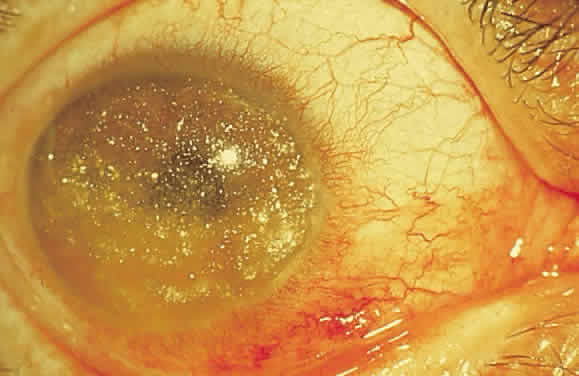

cheese.”10  Fig. 24. A. Histologic section of cytomegalic inclusion retinitis. The characteristic

inclusions cannot be seen at this magnification. Compare the appearance

of viable healthy retina (left of arrow) with necrotic retina (right of arrow). The admixture of necrotic retina (clinically white) with hemorrhage (clinically

red) accounts for the ophthalmoscopic appearance of this entity. B. Cytomegalovirus retinitis. Histologic section of sensory retina demonstrating

massive necrosis involving all layers. (Courtesy of Ralph C. Eagle Jr, MD, Philadelphia, PA) Fig. 24. A. Histologic section of cytomegalic inclusion retinitis. The characteristic

inclusions cannot be seen at this magnification. Compare the appearance

of viable healthy retina (left of arrow) with necrotic retina (right of arrow). The admixture of necrotic retina (clinically white) with hemorrhage (clinically

red) accounts for the ophthalmoscopic appearance of this entity. B. Cytomegalovirus retinitis. Histologic section of sensory retina demonstrating

massive necrosis involving all layers. (Courtesy of Ralph C. Eagle Jr, MD, Philadelphia, PA)